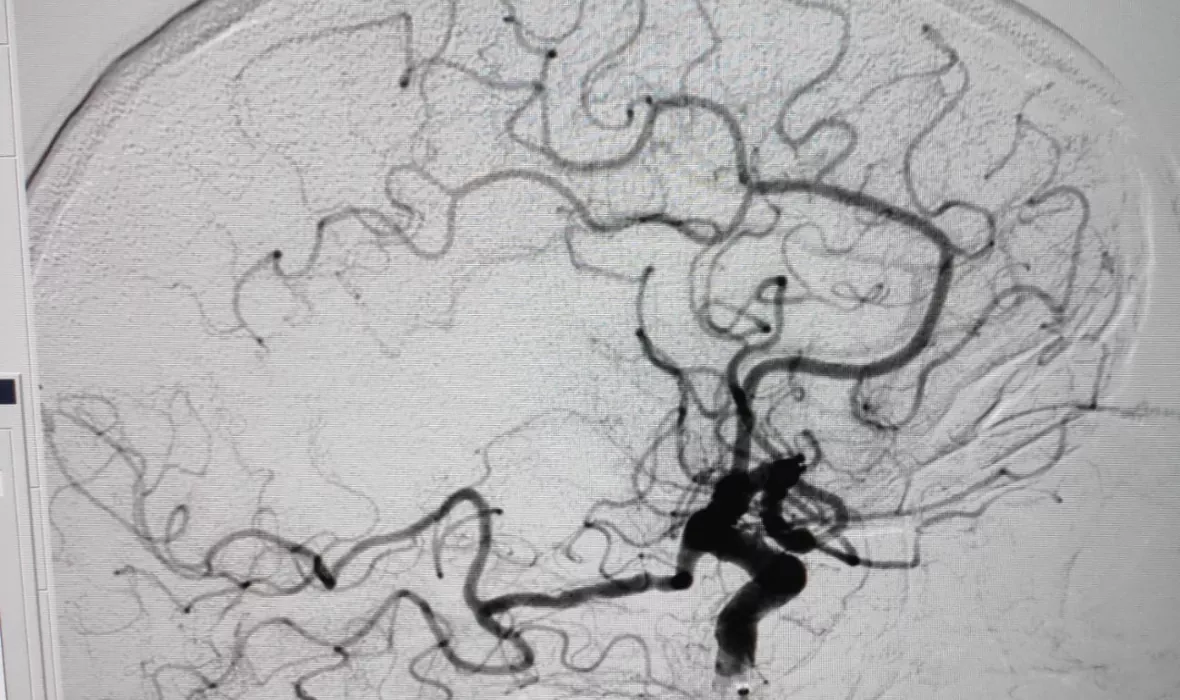

Aquest mes d’octubre, els serveis de Neurologia, Radiologia i Anestesiologia de l’Hospital Universitari Dr. Josep Trueta han realitzat la trombectomia mecànica número 100 en pacients que han patit ictus isquèmic agut amb oclusió arterial de gran vas per un trombe. Aquest procediment consisteix en la introducció d’un catèter en una artèria del pacient per arribar fins al coàgul que l’obstrueix –i que ha produït l’ictus– i poder-lo extreure.

Aquest mes d’octubre s’ha arribat al tractament endovascular de l’ictus isquèmic agut número cent, amb uns resultats molt bons i d’acord amb els indicadors de qualitat establerts pel Pla director de malalties cerebrovasculars i el CatSalut, ja que s'ha aconseguit recuperar un de cada dos pacients tractats que patien un ictus molt greu. Aquests procediments es fan en una sala equipada amb tecnologia específica: la sala d’intervencionisme. En el 85% dels 103 casos realitzats fins ara, s’ha aconseguit una recanalització arterial cerebral i s’ha pogut extreure el trombe que ocloïa el vas, recuperant així la perfusió cerebral.